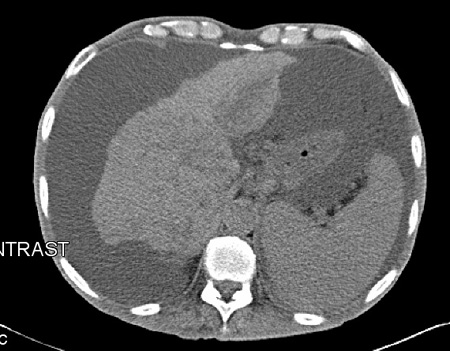

Os pacientes apresentam distensão abdominal; o líquido pode ser detectado ao exame físico como macicez móvel. A ultrassonografia, a tomografia computadorizada (TC) ou a ressonância nuclear magnética (RNM) podem confirmar o diagnóstico. Na maioria dos pacientes, a história e o exame fornecerão pistas importantes sobre a etiologia da ascite (por exemplo, sinais de doença hepática crônica ou de insuficiência cardíaca). As causas incluem doenças que causam hipertensão portal, a hipoalbuminemia e as neoplasias.